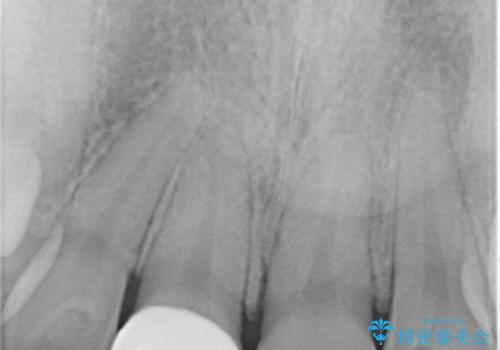

- プラスチックで治療している前歯が何度も欠けてしまうとお悩みで来院された方です。

歯全体を覆うクラウンにて治療を行いました。

前歯1本のみの被せ物治療を行う場合、他の歯を参考に歯の色や形を忠実に再現することが重要です。オールセラミッククラウン(スペシャル・エクセレント)は、事前に歯科技工士との打ち合わせを行うことで、歯の色や形、さらには患者様のご希望も聴取したうえでクラウンを作製することが可能です。